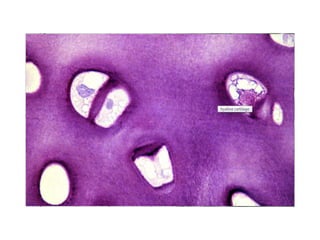

Cartilago

ESTRUCUTRA DEL PERICONDRIO

3.

PERICONDRIO CFE CCI CRECIMIENTOAPOSICIONAL CRECIMIENTO INTERSTICIAL